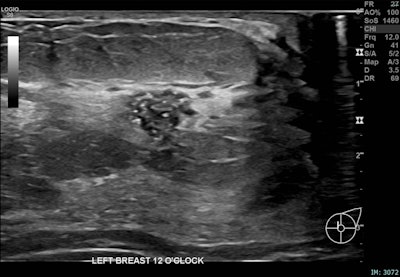

Correlative mammographic, sonographic and histopathological findings in a 29-year-old woman presenting with a palpable left axillary lump, subsequently shown to be accessory breast tissue. (a) Ultrasound, left breast, 12 o’clock position: A 10 mm partially irregular hypoechoic lesion with internal calcific foci, located 1 cm from the nipple.Courtesy Atienza-Hipolito and Alderman; RANZCR